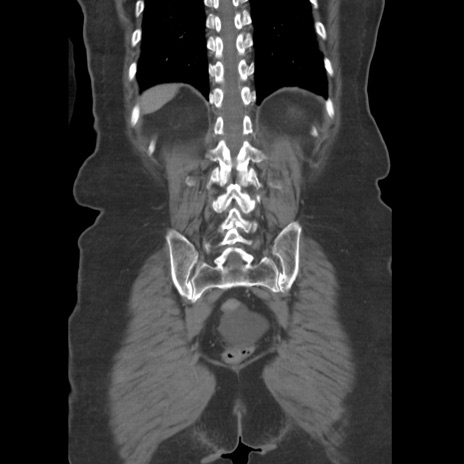

症例19(冠状断像)

【症例】80歳代女性

【主訴】下腹部痛

【現病歴】約8時間前より下腹部痛の出現あり、救急外来受診。

【既往歴】両側付属器切除

【身体所見】意識清明、下腹部正中に手術痕あり、その部位に一致して圧痛と反跳痛あり。腸蠕動音は亢進。

【データ】WBC 9300、CRP 0.15